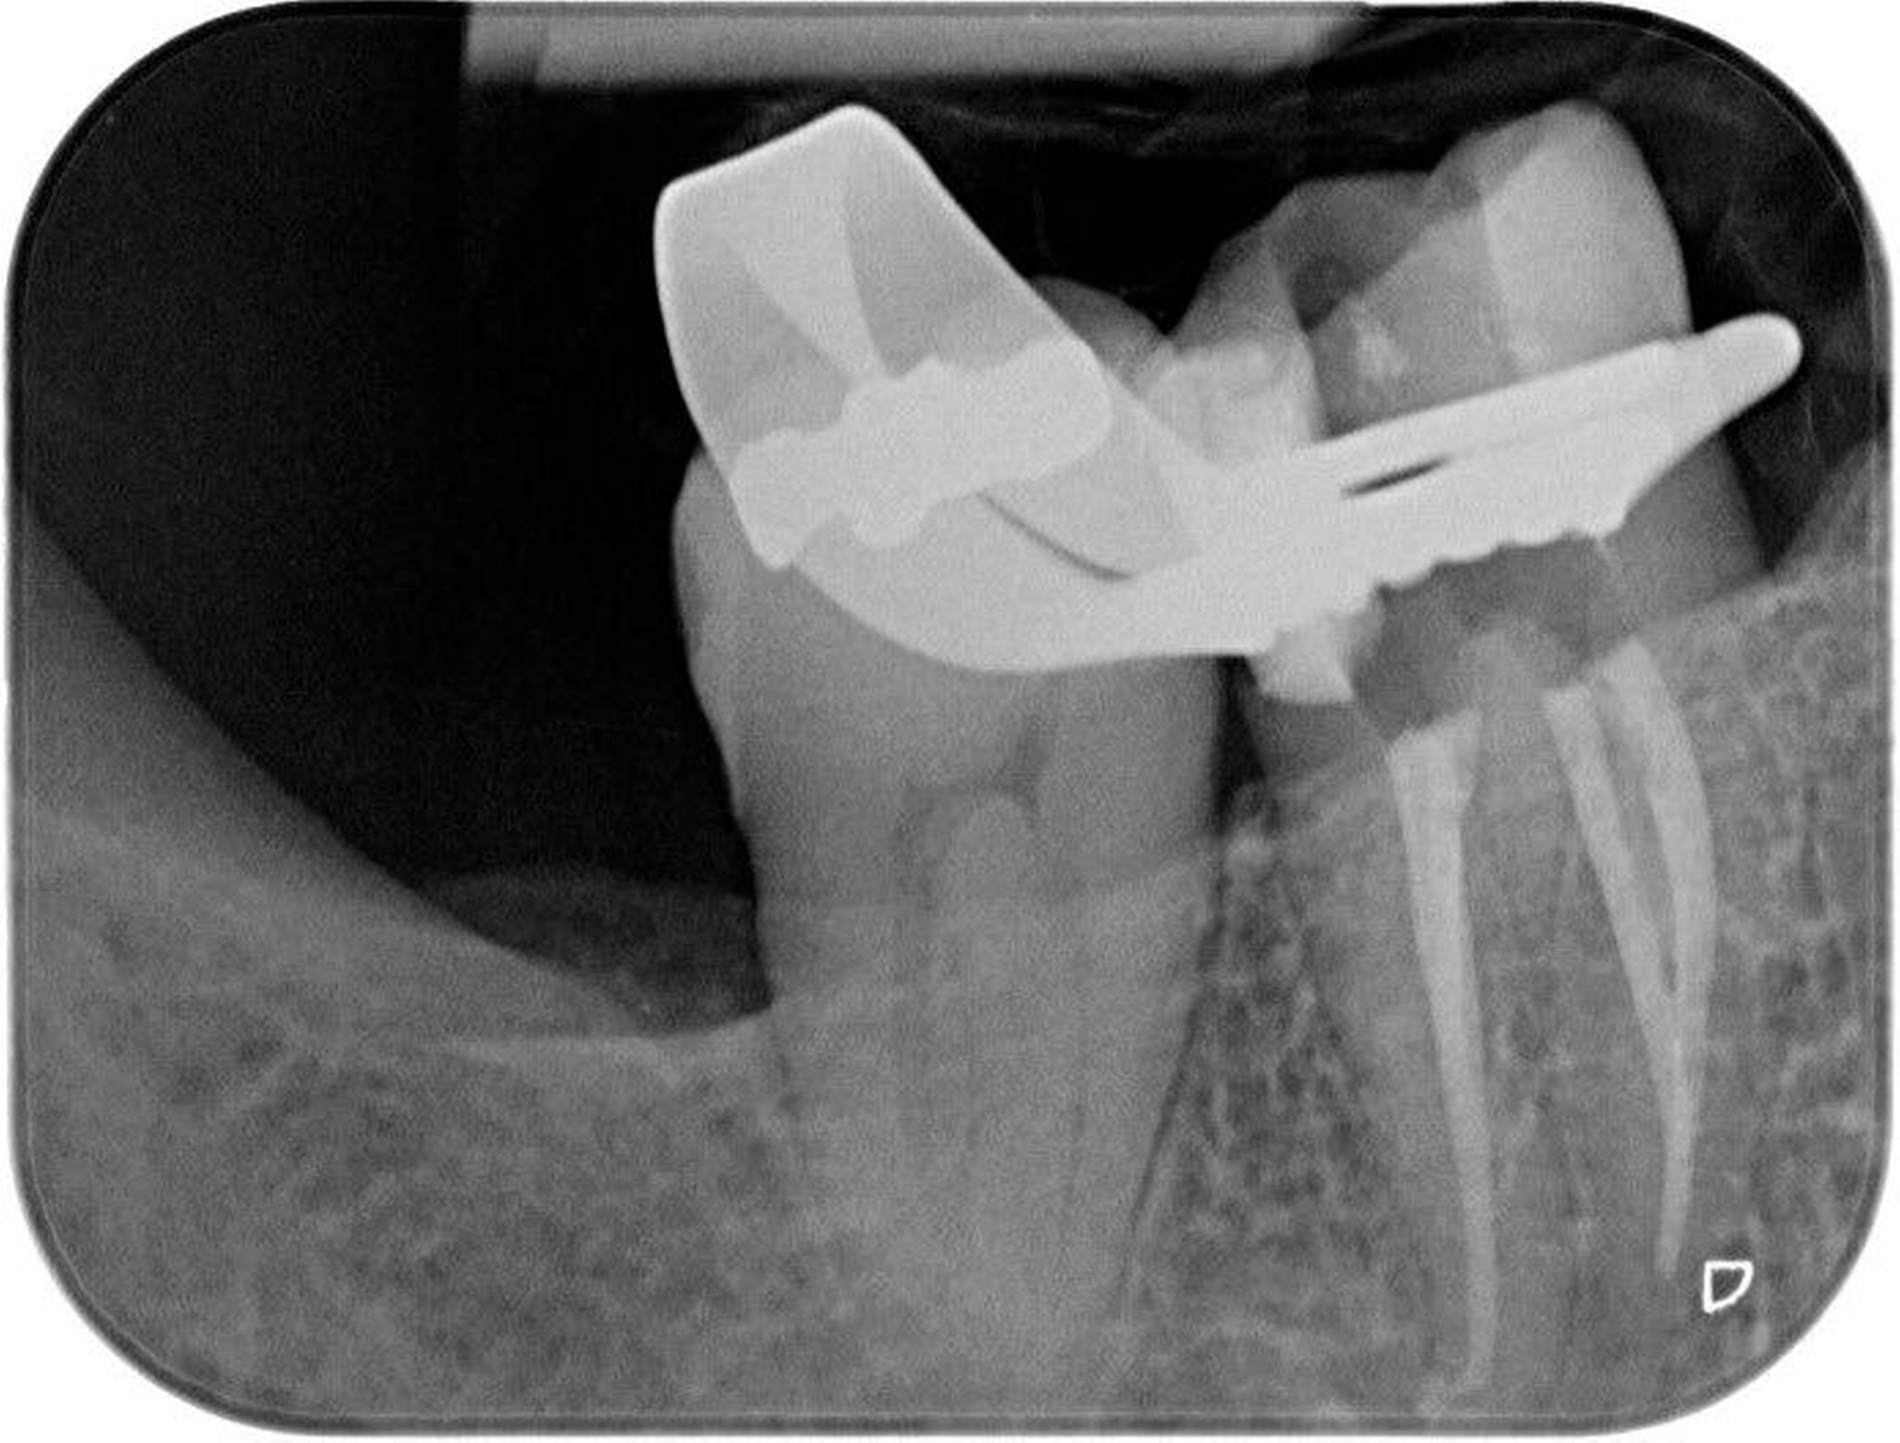

Die Wurzelkanalbehandlungen der Preisträgerer wurden als exzellent eingestuft, da sie einen besonders hohen Schwierigkeitsgrad aufwiesen. Dazu gehören schwierige Ausgangssituationen, etwa bei Durchführung einer Wurzelkanalrevision, bei der eine bereits vorhandene Wurzelkanalbehandlung revidiert werden muss. Auch anatomische Besonderheiten, wie zwei Wurzelkanäle in einer Wurzel, stellen eine besondere Herausforderung dar und bedürfen einer besonders aufwendigen Behandlung.